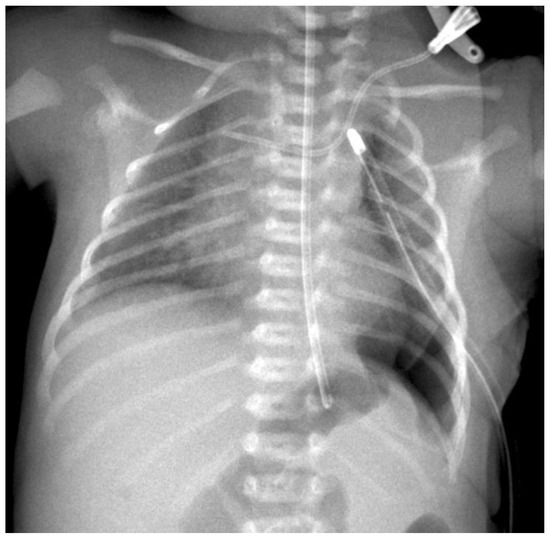

A control X-ray is taken on the ICU 2–4 h after the end of the operation (see Figure 6). All operations were conducted by the same surgeon.

Figure 6. The postoperative radiograph.